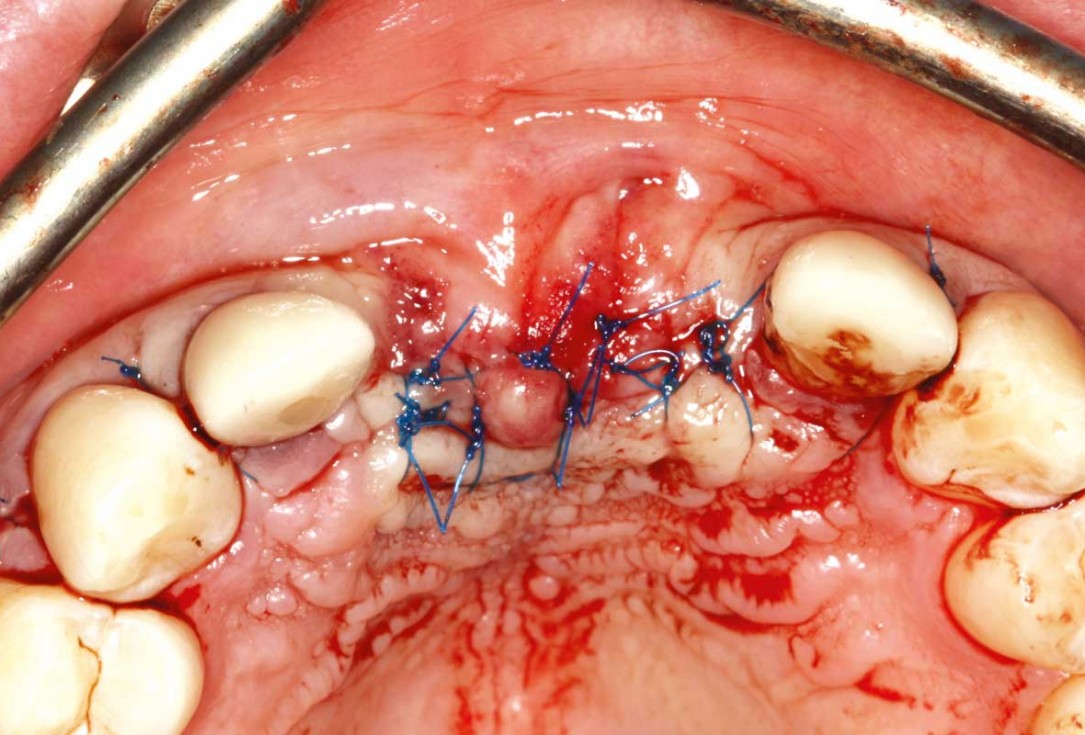

09/26 - Wound closure with 15 sutures

Ridge augmentation in the maxilla with maxgraft® bonebuilder in the aesthetic zone - Dr. M. Kristensen